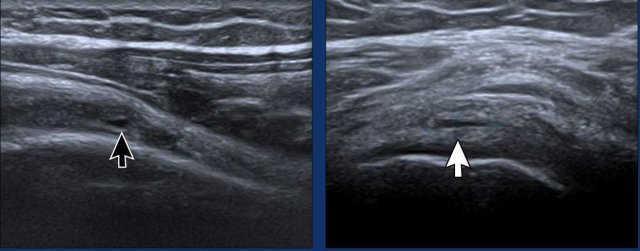

Image during exoratation (left) and endorotation (right) Image during exoratation (left) and endorotation (right)

Impingement

During endorotation a normal subscapular tendon should show almost complete passage underneath the coracoid process.

Impingement is suspected when a residual portion of the tendon is still visible during maximum endorotation.

Images

During endorotation there is incomplete passage under the coracoid and buckling of the subscapular tendon.